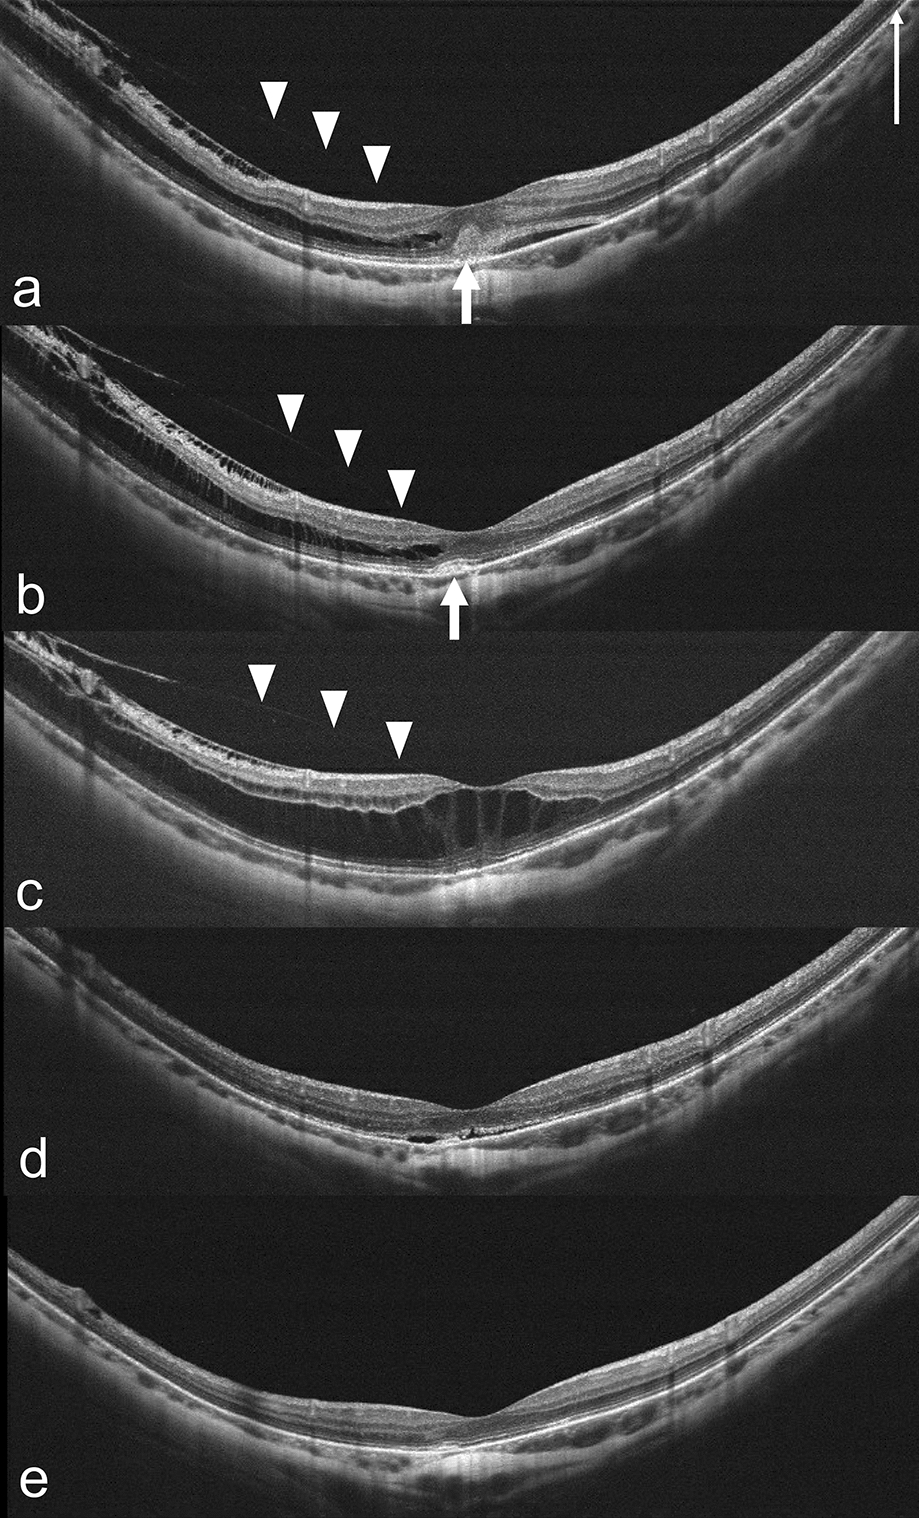

Of the 295 eyes, 13 showed progression, with 15.4% of these progressing to FTMH (1 case is shown in Fig. 1), 15.4% to FD (1 case is shown in Fig. 2), 30.8% to macular hole retinal detachment (MHRD), 7.7% to LMH, and 30.8% to other conditions at risk of vision threatening, such as foveoschisis shaped like a champagne flute [12, 13, 26] (1 case is shown in Fig. 3). Consequently, these eyes received surgical intervention at 12.7 ± 9.1 months (range 2–34 months, median 10 months) after initial injection. (Table 2). One eye (Fig. 3) received IV perfluoropropane (C3F8) [27, 28] and the other 12 eyes received pars plana vitrectomy combined with the inverted ILM flap technique [29, 30] (5 eyes; 1 case is shown in Fig. 1), the center non-peeling ILM surgery technique [3134] (3 eyes), or simple ILM peeling (4 eyes; 1 case is shown in Fig. 2). Of the 13 eyes with progression, 11 (84.6%) had MRS at baseline. Risk factors for vision-threatening MRS requiring surgical intervention in eyes with progression and onset of MRS were evaluated by using logistic regression models (Table 3). AL, AL of fellow eye, initial CFT, myopic maculopathy category at baseline, and presence of foveoschisis, inner retinal schisis, ERM, and LMH at baseline were identified to be risk factors, while intravitreal ranibizumab (IVR) and presence of retinal hemorrhage at baseline were protective factors. Eyes requiring surgical intervention compared to those with no need of surgical intervention had poorer BCVA at 1 month after injection (logMAR 0.757 ± 0.363 vs. logMAR 0.510 ± 0.410, p = 0.026), at 6 months (logMAR 0.799 ± 0.402 vs. logMAR 0.521 ± 0.451, p = 0.011), at 1 year (logMAR 0.882 ± 0.528 vs. logMAR 0.530 ± 0.413, p = 0.012), and at the last follow-up visit (logMAR 1.038 ± 0.767 vs. logMAR 0.667 ± 0.624, p = 0.030), and had greater CFT at 1 month (370.7 ± 147.5 vs. 274.9 ± 57.9 µm, p = 0.009), at 3 months (353.4 ± 129.9 vs. 268.8 ± 56.6 µm, p = 0.003), and at 6 months (415.8 ± 196.5 vs. 274.5 ± 52.1 µm, p = 0.001). In addition, the former had higher ratios of categories 3 and 4 myopic maculopathy at the last follow-up visit. We also found that there was no association of age, gender, initial BCVA, location of CNV, the number of total injections, the number of intravitreal bevacizumab (IVB), IVR, and intravitreal aflibercept (IVA) injections, as well as presence of lacquer cracks, punctate inner choroidopathy (PIC), staphyloma, MRS, outer retinal schisis, VMT, VMA, and dome-shaped macula at baseline (p > 0.05 for all) (Table 3). In eyes with MRS progression requiring surgery, the progression was found in the following ratios: 53.8% in the outer retinal layers, 23.1% presence of LMH, 7.7% in both the outer and inner retinal layers, 7.7% in inner retinal layers, and 7.7% presence of FTMH.

Fig. 2

Progression of MRS in the right eye of a 53-year-old woman with mCNV. a Before anti-VEGF treatment, subfoveal mCNV (arrow) and outer retinal schisis were shown on OCT. BCVA was 20/100. b 2 months after 2 injections of IVB, mCNV became smaller (arrow), BCVA improved to 20/40, and MRS remained stationary. c 6 months after injections, MRS progression to foveal detachment (FD) (asterisk) was observed, and BCVA decreased to 20/67. d 6 months after pars plana vitrectomy and ILM peeling, FD and MRS improved. e 1 year after operation, resolution of FD and improvement of MRS were noted on OCT. f 2 years after operation, attached retina without MRS was observed and BCVA was 20/50